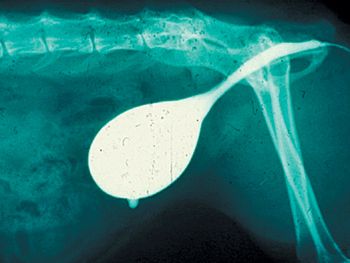

A recent study sought to establish the incidence of and risk factors for seizures after myelography with iohexol in dogs.